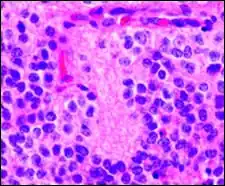

Гистопатологический образец нейробластомы с розетками Гомера Райта, окраска гематоксилин-эозин